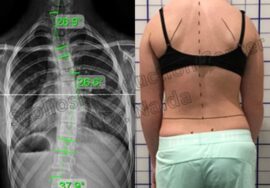

بعض الأطباء ينصحون بالجراحة عند تجاوز زاوية الانحناء 45 إلى 50 درجة، ظنًا أن الجراحة الحل الأمثل لتقويم العمود الفقري بسرعة. لكن الجراحة ليست دائمًا الخيار الأفضل، فهي تحمل مخاطر ومضاعفات، وقد تؤثر على مرونة العمود الفقري لاحقًا.

تُعرف باسم “دمج الفقرات” أو Spinal Fusion، حيث يتم تثبيت فقرات العمود الفقري باستخدام قضبان ومسامير لمنع الانحناء من التزايد. رغم فعاليتها في السيطرة على الانحناء، إلا أنها لا تعيد العمود الفقري إلى استقامته الكاملة دائمًا. التعافي من الجراحة قد يستغرق أشهرًا، ويُفقد المريض جزءًا من مرونة الظهر، ما قد يقيّد الأنشطة اليومية لاحقًا.

حتى بعد الجراحة، قد يبقى هناك انحناء بسيط، وبعض المرضى يعانون من تيبّس أو آلام مزمنة. في بعض الحالات، قد يحتاج المريض إلى جراحة تصحيحية مستقبلية. لهذا، يوصي الخبراء عالميًا بمحاولة العلاجات غير الجراحية أولًا، خصوصًا في حالات الجنف مجهول السبب عند المراهقين.

العلاج غير الجراحي يتطلب التزامًا من الأهل والمريض ومراقبة دقيقة للانحناء باستخدام الأشعة وتحليل زاوية “كوب” (Cobb Angle). هذه المتابعة تضمن تعديل خطة العلاج بما يتناسب مع تطور الحالة.

تابعوا قياسات زاوية “كوب” لضمان فعالية العلاج.